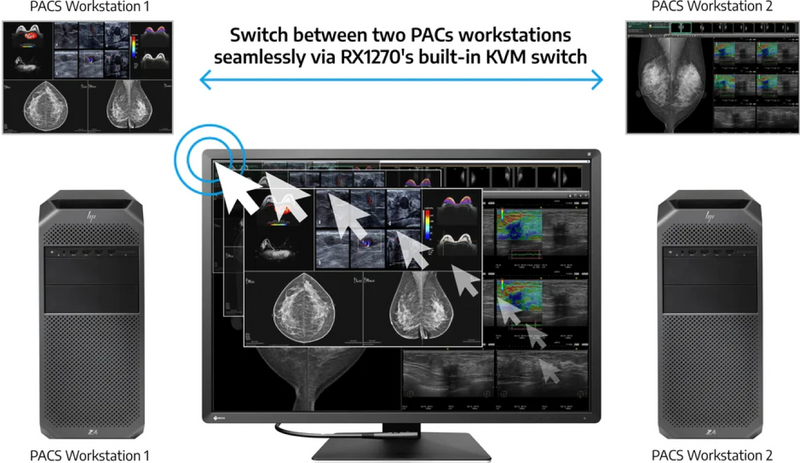

Η συνάρτηση switch-and-go στο Radiforce RX1270 Eizo επιτρέπει την εναλλαγή USB μέσω της οθόνης, επιτρέποντας τη χρήση ενός ενιαίου πληκτρολογίου και ποντικιού σε δύο συνδεδεμένους υπολογιστές. Αυτό είναι βολικό για περιβάλλοντα διπλής οθόνων/υπολογιστή ή μεταβαλλόμενες εισόδους σε μία μόνο οθόνη που συνδέεται με δύο υπολογιστές.

Επιπλέον, μπορείτε να χρησιμοποιήσετε το Switch-and-Go με το Hide-and-Sek για να εμφανίσετε την οθόνη ενός φορητού υπολογιστή (συνδεδεμένο μέσω HDMI) ως ξεχωριστό παράθυρο στην οθόνη. Το παράθυρο μπορεί να κρυφτεί ή να εμφανίζεται στην εντολή χρησιμοποιώντας ένα μόνο ποντίκι και πληκτρολόγιο για να αποκτήσετε πρόσβαση σε περισσότερες πληροφορίες γρήγορα.